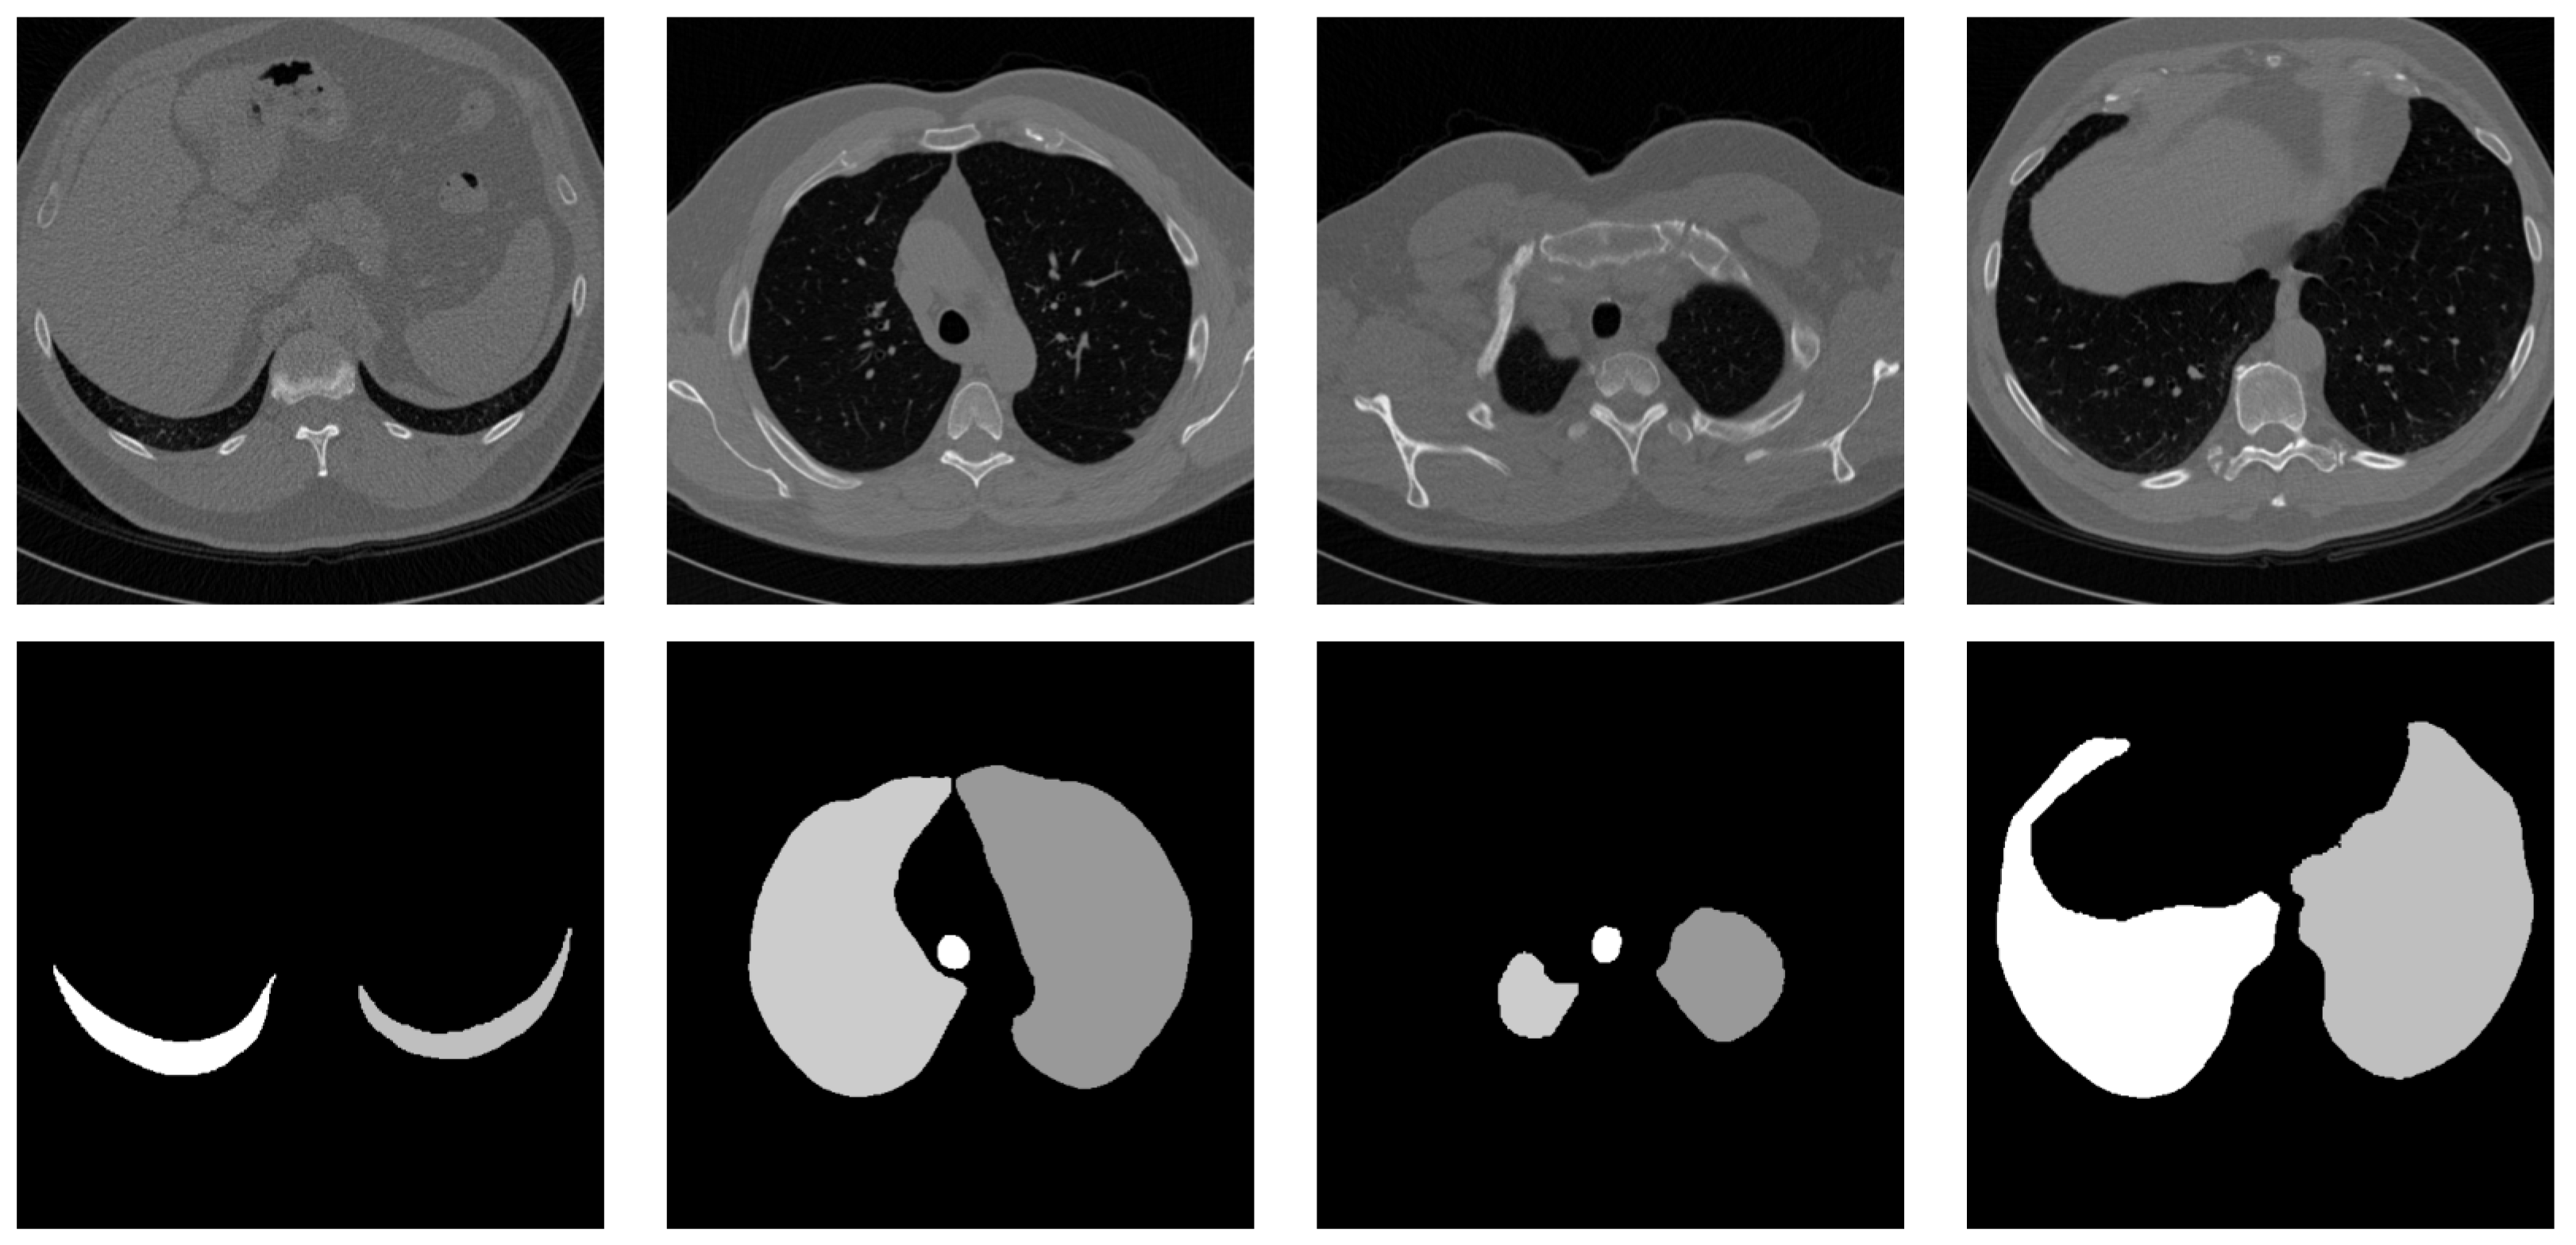

3.1. Dataset and Preprocessing

- Isotropic resampling (for 3D images): We first resampled each CT volume to an isotropic voxel spacing of 1 × 1 × 1 mm using linear interpolation. This step, performed using linear interpolation functions available in standard imaging libraries, ensures that spatial relationships between voxels are consistent across all dimensions, regardless of the original slice spacing.

- Slice-by-slice processing: Each 3D volume was then processed slice by slice. This approach allows us to apply SALM, designed for 2D inputs, to 3D volumetric data. While the Vision Transformer processes each slice independently, the modified 3D positional encoding, described in detail in Section 3.2.2, allows for the integration of 3D spatial context.

- Resizing to 1024 × 1024: Each slice, whether from an original 2D image or extracted from a 3D volume, was resized to a standard size of 1024 × 1024 pixels using linear interpolation (linear interpolation). This resizing operation ensures that the model receives input images of uniform dimensions, which is crucial for the performance of the Vision Transformer. The choice of the 1024 × 1024 size represents a compromise between preserving anatomical details and memory and computational constraints.